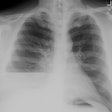

The lesion typically presents with a pleural effusion with associated smooth, nodular pleural thickening (resembling a mesothelioma).